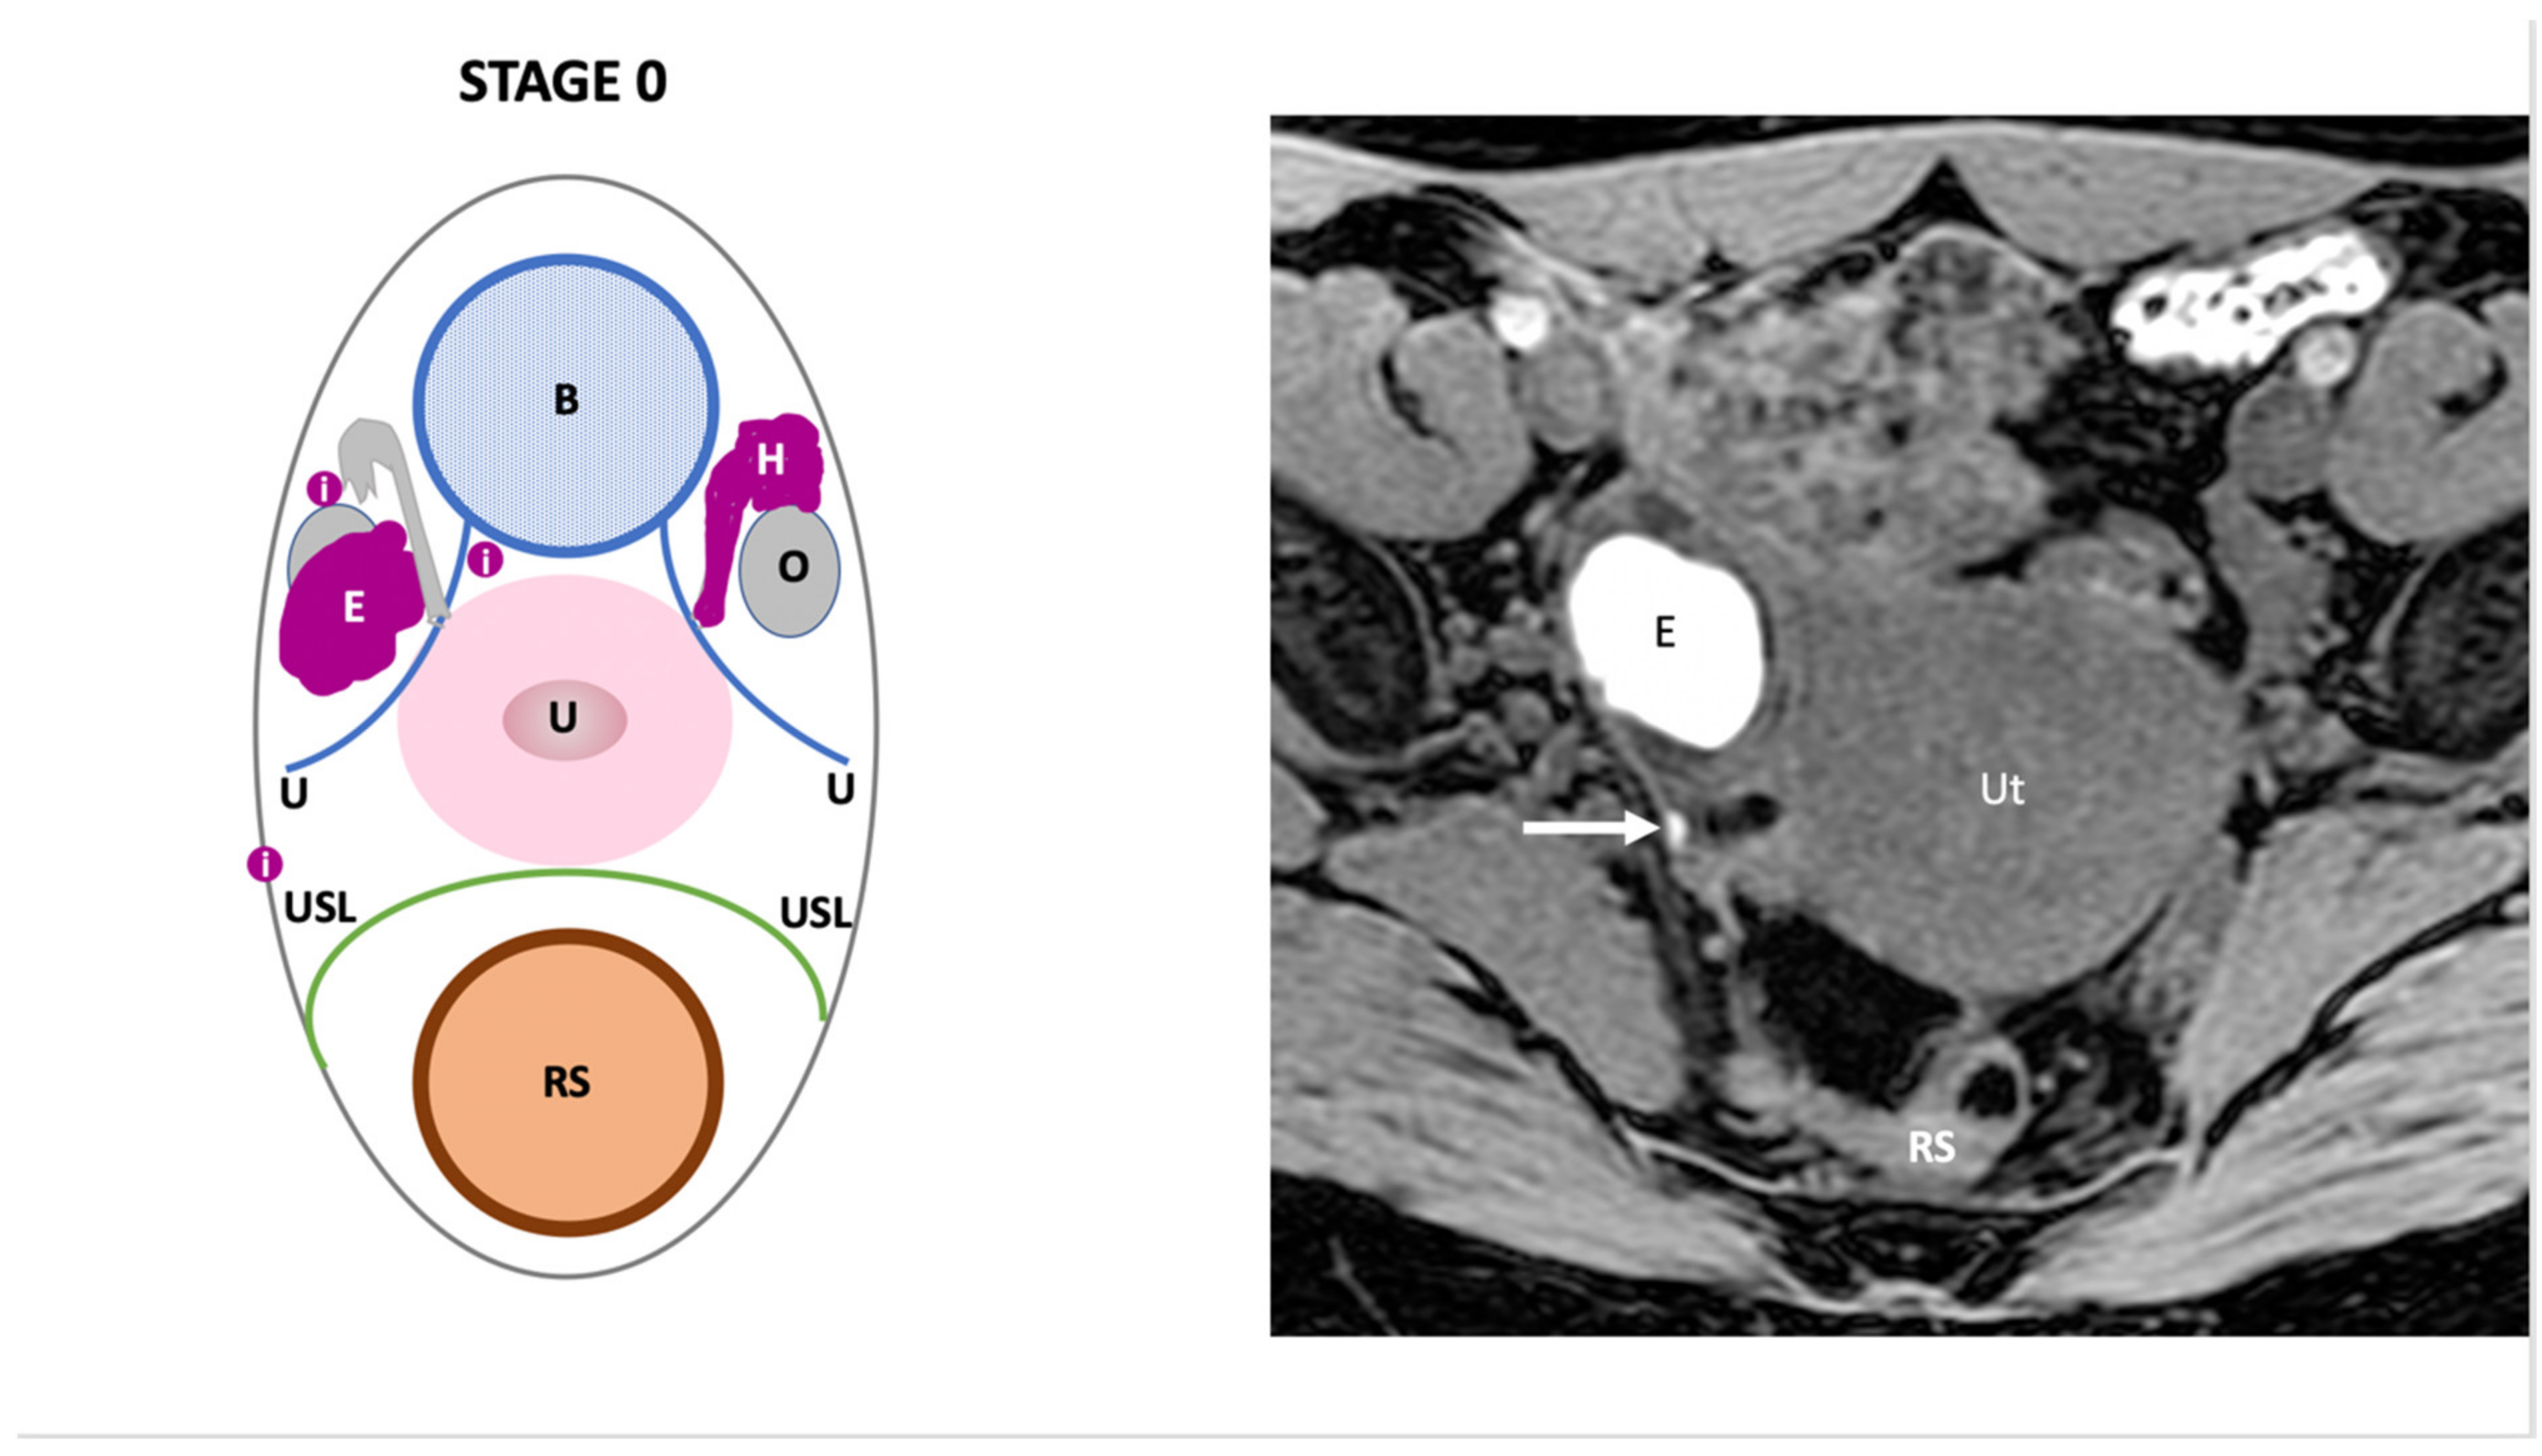

| Endo-Stage MRI 0 | Superficial endometriosis |

| Low |

| Endometriosis is strictly confined to the ovaries |